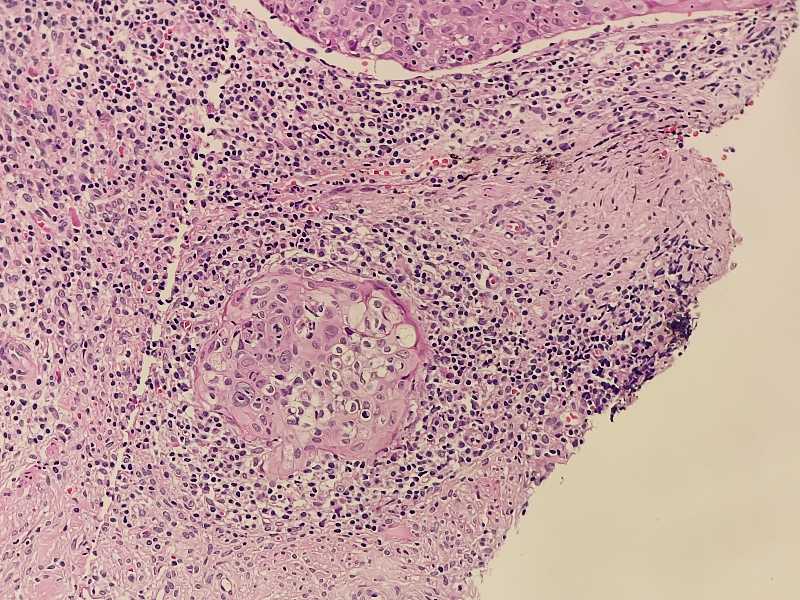

女40岁宫颈锥切组织浸润还是CIN累腺

女40岁宫颈锥切组织 浸润还是CIN累腺?

考虑:鳞癌